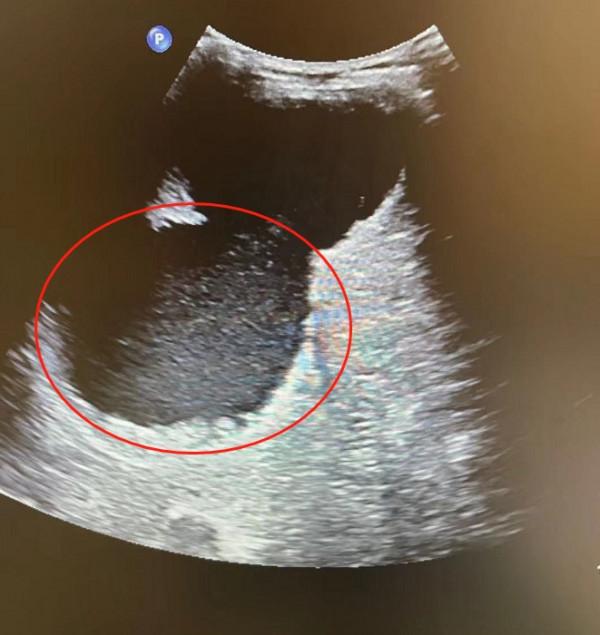

55歲的卞阿姨(化名)一年前發現自己右上腹鼓起了一大塊,從那時開始,她不僅每天食慾不振吃不下飯,慢慢地連呼吸都受到了影響。8月30日,深圳市第三人民醫院(南方科技大學第二附屬醫院)為卞女士做了超聲檢查,發現卞女士肝上長出了一個18釐米的巨大囊腫,超聲科主任李志豔形容這個囊腫“像個裝滿水的快要爆掉的氣球一樣,岌岌可危!”

住院以後,深圳市三院給卞女士做了更詳細的檢查。結果顯示,導致卞女士囊腫迅速長大的“元兇”是囊內出血,此時這個囊腫已經長到了18釐米,接近一個排球大小,不僅向上頂起了膈肌壓迫到了胸腔,還向下推擠腹部,在肋下隆起,所以卞女士才會食慾不振、呼吸不暢。如果不進行置管引流,巨大囊腫不僅會嚴重影響她的生活質量,還有可能發生破潰和繼發感染等問題。

對於這樣巨大的囊腫,不僅要求操作醫生有嫻熟的穿刺技術,還要有干預繼發性出血的能力。“卞女士的囊腫就像一個巨大的、裝滿水的氣球,已經岌岌可危了,置管引流就是要在不弄爆這個‘氣球’的前提下,將裡面的水都放出來。”李志豔說。